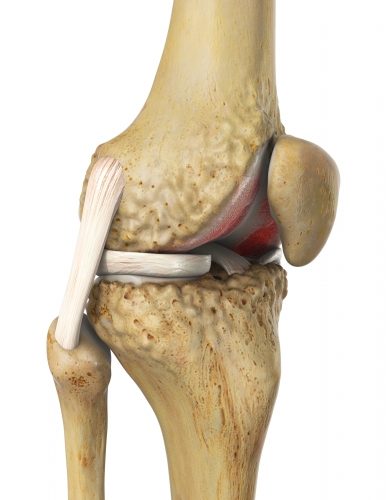

In frühen Stadien der patellofemoralen Arthrose kann eine Änderung der Zugstärke und Zugrichtung der verschiedenen Bänder, die die Patella führen, die Symptomatik verbessern. Je nachdem, welcher Bereich hinter der Patella besonders betroffen ist, stehen unterschiedliche Arten von Operationen an den Sehnen zur Verfügung. Mittels Verkürzung oder Verlängerung der Sehne kann der Orthopäde die Lage der Patella in der femoralen Gleitrinne anpassen.

Autologe Knorpeltransplantation

Bei der Knorpelzelltransplantation wird körpereigener Gelenkknorpel des Patienten in die Knorpelschäden hinter der Patella eingebracht. Solange die Knorpelschäden nur eine der beiden Gelenkfläche betreffen, ist diese Therapie noch möglich.

Bei kleinen Knorpelschäden besteht die Möglichkeit, den Knorpel hinter der Patella wieder nachwachsen zu lassen. In einer arthroskopischen Operation wird ein kleines Knorpelstück (etwa die Menge eines Reiskorns) aus einem wenig belasteten Teil des retropatellaren Knorpels herausgelöst. Diese Knorpelmasse wird in einem Speziallabor vermehrt. Nach 6 bis 8 Wochen werden diese Zellen in einem weiteren arthroskopischen Vorgehen direkt auf die Schadstellen hinter der Patella aufgebracht. In ca. 3 Monaten differenzieren sich die Knorpelzellen wieder zu festem, wasserbindendem und stabilem Knorpelgewebe aus. Diese autologe Knorpeltransplantation (Verpflanzung von körpereigenem Knorpelzellen des Patienten) kommt vor allem für jüngere Patienten infrage. Die Regeneration der Knorpelschicht kann eine Arthrose häufig noch abwenden und gerade jüngeren Patienten unter 50 Jahren eine patellofemorale Prothese ersparen.